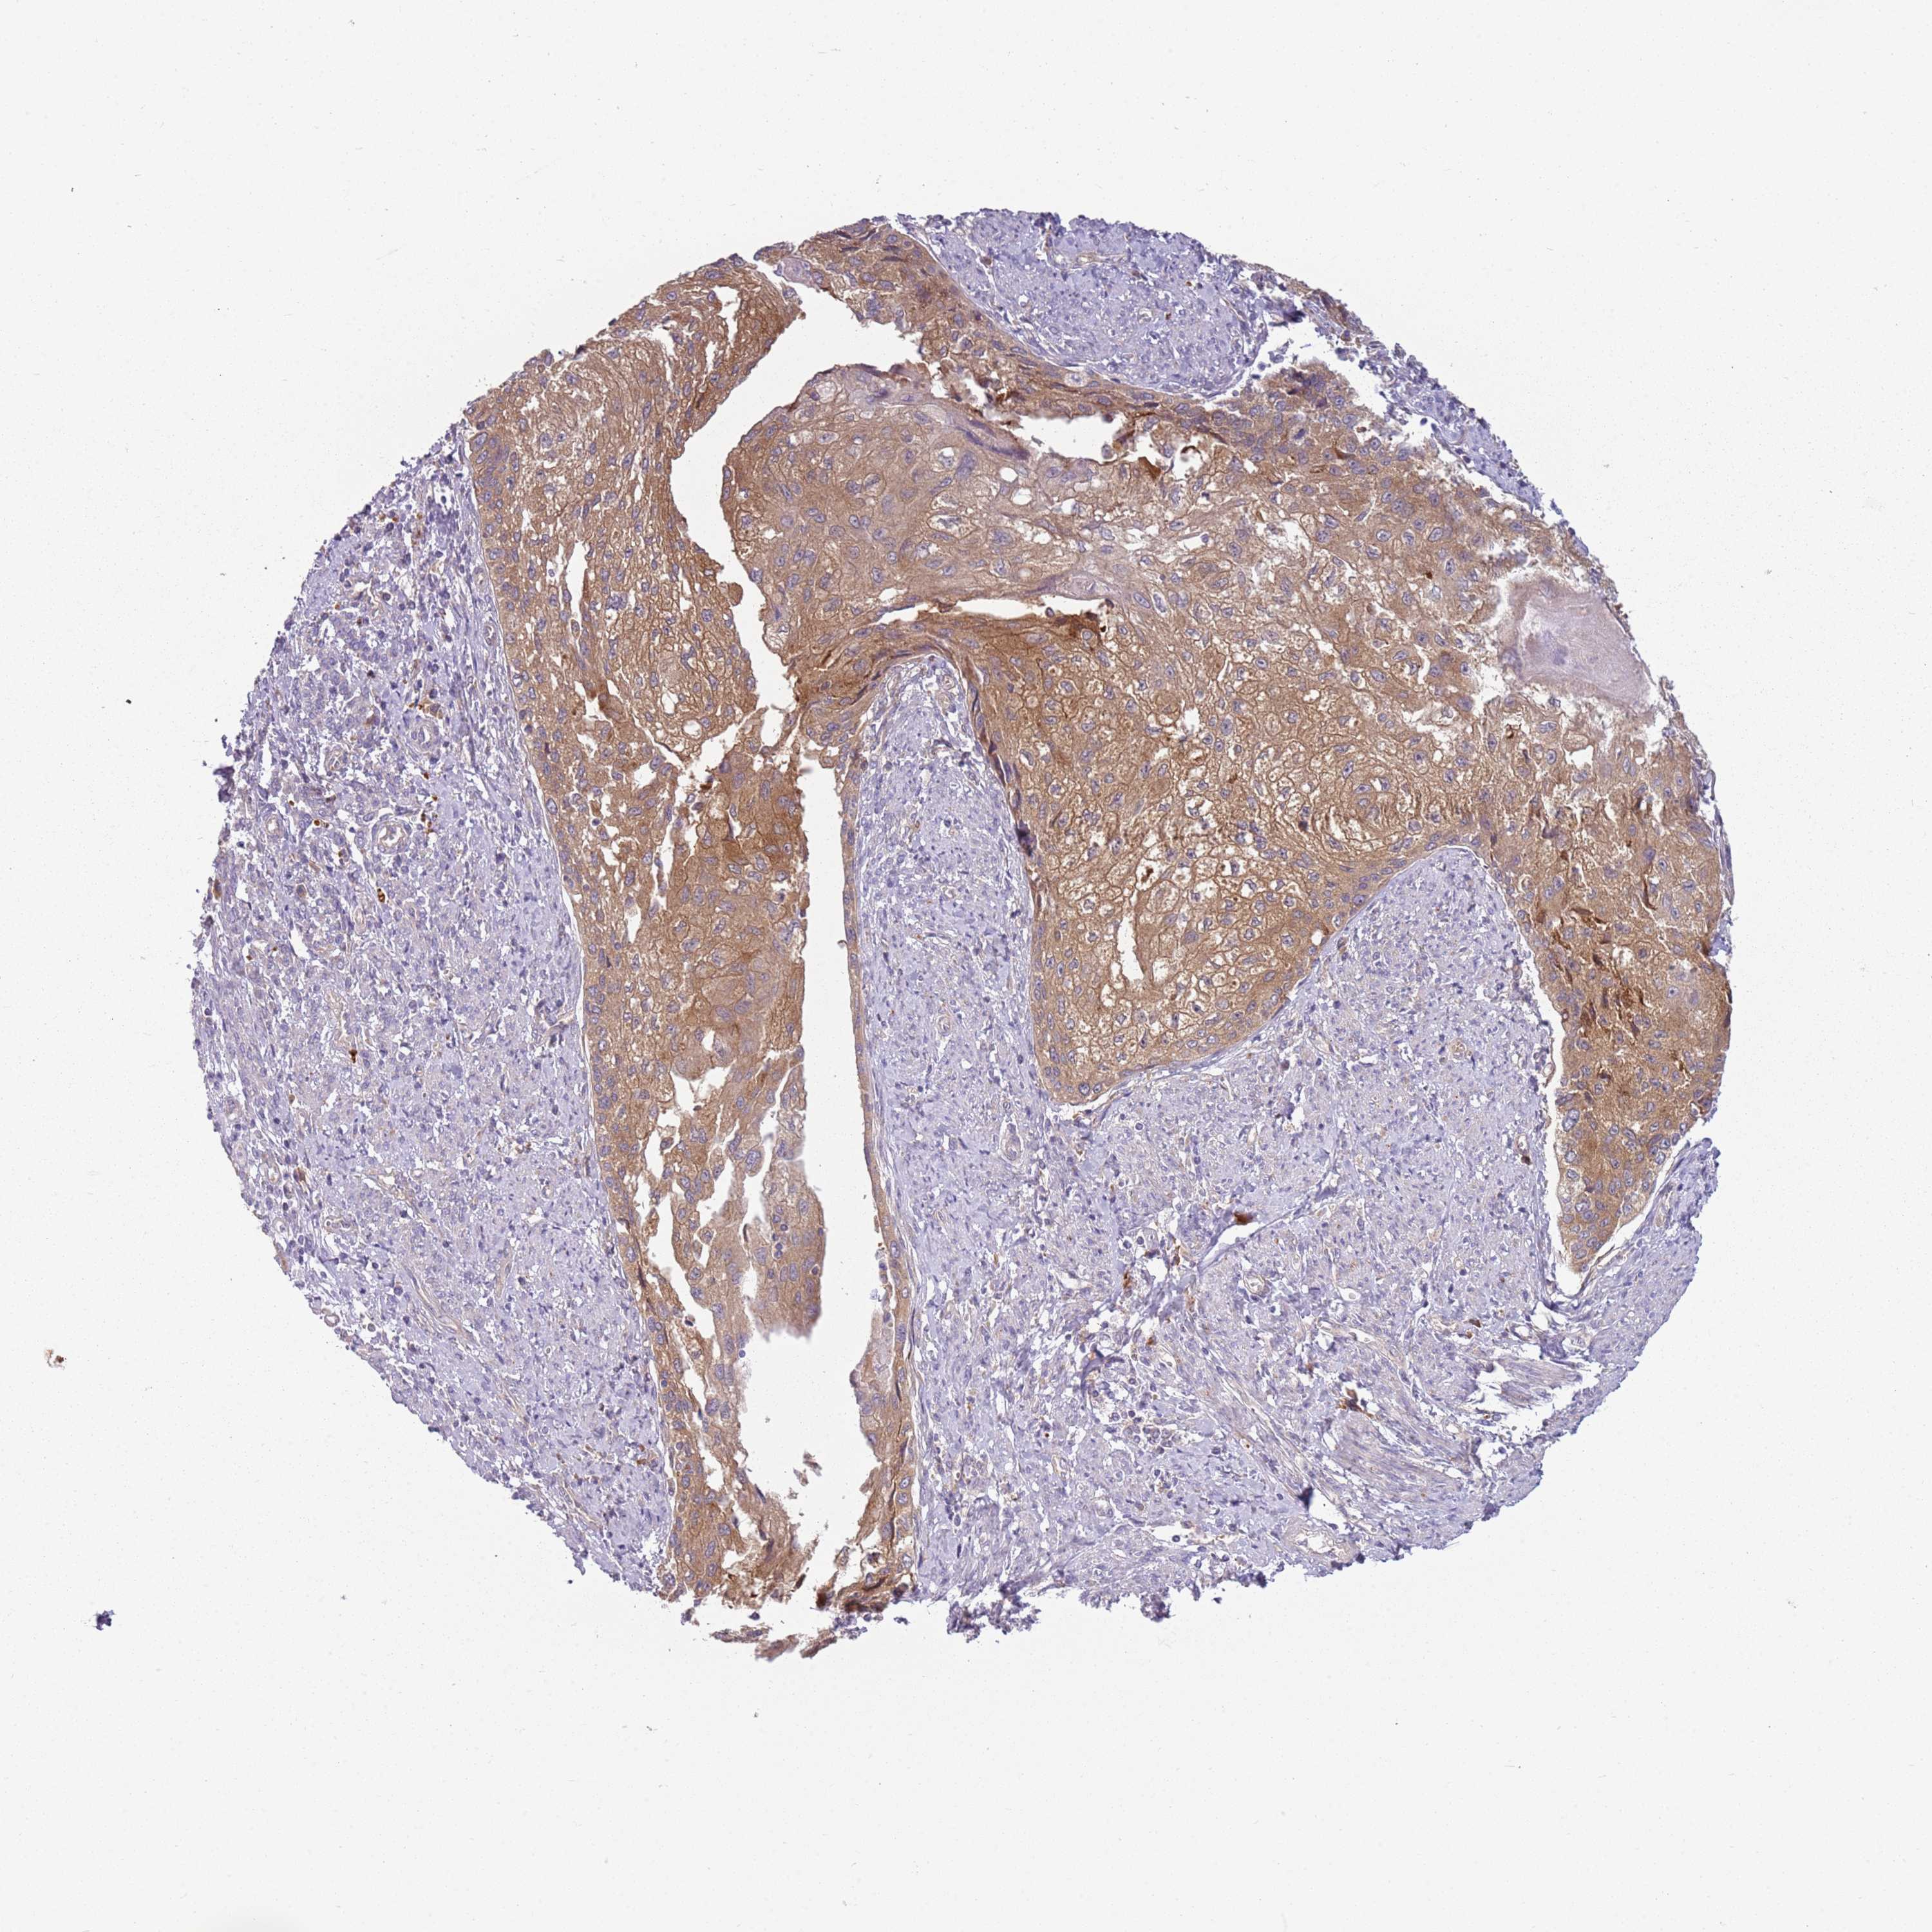

CERVICAL CANCER - Protein expressioni

A mouse-over function shows sample information and annotation data. Click on an image to view it in a full screen mode. Samples can be filtered based on level of antibody staining by selecting one or several of the following categories: high, medium, low and not detected. The assay and annotation is described here.

Note that samples used for immunohistochemistry by the Human Protein Atlas do not correspond to samples in the TCGA dataset.

Antibody stainingi

Antibody staining in the annotated cell types in the current human tissue is reported as not detected, low, medium, or high, based on conventional immunohistochemistry profiling in selected tissues. This score is based on the combination of the staining intensity and fraction of stained cells.

Each image is clickable and will lead to virtual microscopy that enables deeper exploration of all samples and also displays staining intensity scores, fraction scores and subcellular localization as well as patient and tissue information for each sample.

Antibody HPA047132

Staining

High

Medium

Low

Not detected

Intensity

Strong

Moderate

Weak

Negative

Quantity

>75%

75%-25%

<25%

None

Location

Nuclear

Cytoplasmic/membranous

Cytoplasmic/membranous,nuclear

Squamous cell carcinoma, NOS

Adenocarcinoma, NOS